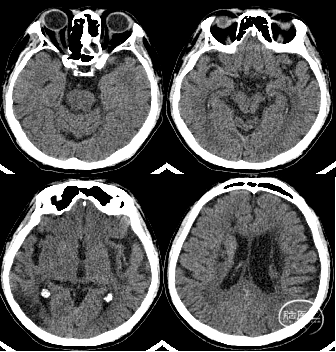

术后CT:后循环区域未见出血及造影剂染色。颅内多发陈旧性梗死病灶。

举例图片,非上述病例患者